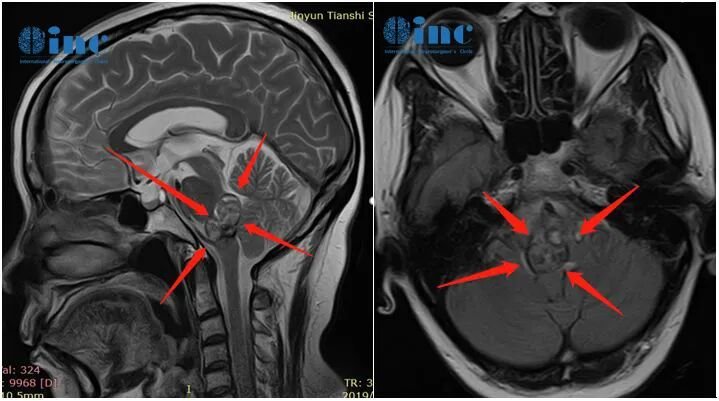

最终患者及时选择手术并获得成功。类似案例中,50多岁黄女士10年间经历6次出血,3次生命垂危,曾在ICU治疗60余天。黄女士出现肢体麻木、头晕、耳鸣、视力下降、吞咽困难等症状。虽最终经巴教授成功手术,但多次出血导致的神经损伤已无法完全恢复,仅能缓解症状;此次手术及时挽救了患者生命。

黄女士通过亲身经历告知患者:若海绵状血管瘤患者在保守治疗过程中病情加重或病灶增大。若手术指征明确,不应拖延时间,尽早手术切除可获得更好预后。切勿延误治疗时机。黄女士强调,经过多年坎坷经历,更加理解生命重要性。"疾病无人喜欢,但患病后只能积极面对争取治疗。作为家属,更应支持关爱患者,创造一切条件,确保患者获得及时有效治疗。"